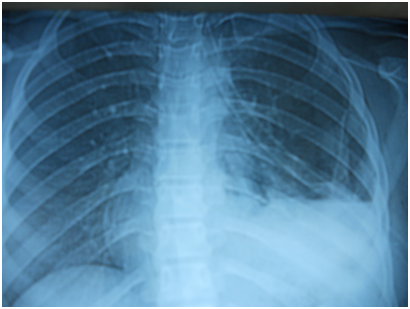

A 17-year-old girl (170cm, 60kg) presented to the emergency department with dyspnea and chest pain after a penetrating stab wound to the chest in the left sixth intercostal space mid-clavicular line, which happened 2hours earlier. Upon physical examination, Pulse was 96 beats per minute and blood pressure was 110/70mmHg, diminished air entry was noticed on the left side of chest. Chest x-ray revealed left hydropneumothorax. Tube thoracostomy was performed left intercostals tube was inserted for drainage. Post-insertion chest x-ray revealed no improvement in the picture of air fluid level (Figure 1) (Figure 2) which was further evaluated by CT that showed fluid collection posteriorly and air anteriorly (Figure 3) (Figure 4). Two days later patient had fever with vomiting and leucocytosis. The nature of the drain from the intercostal tube becomes serosangenous and less hemorrhagic with change in color associated with food. Methylene blue dye (1% concentration) taken orally by the patient was detected in the drain of the intercostal tube two minutes after ingestion (Figure 5). Oral contrast chest x-ray was done, two shots were taken one on swallowing gastrographin, it showed the esophagus outlined without any leakage (Figure 6A). The other shot taken two minutes after oral administration of gastrographin in trendlenberg position, the contrast outlined a track passing from the fundus of the stomach to the left pleural cavity and to the intercostals tube (Figures 6B) (Figure 6C). Laparotomy was performed via midline incision and findings were confirmed. It showed a 3cm orifice of the left copula of the diaphragm with a tear in the gastric fundus which was closed in two layers and the diaphragmatic tear was closed directly with continuous sutures. Two weeks later patient complicated by left empyema with thickened pleura. Thoracotomy was done for complete evacuation of pus and decortication. The patient fully recovered and was discharged 8days after thoracotomy.

Figure 1 Post intercostals tube insertion chest X-ray.

Figure 2 Second day post intercostals tube insertion chest X-ray.